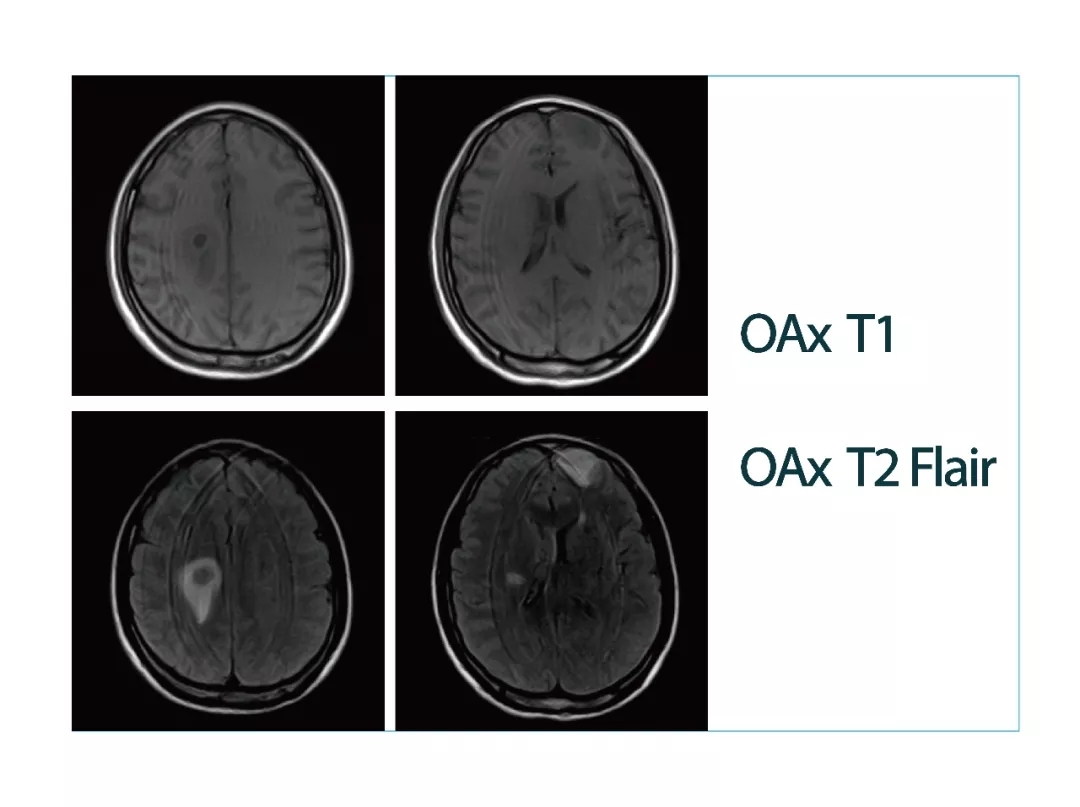

【朗润影像档案】20180413磁共振影像病例分享